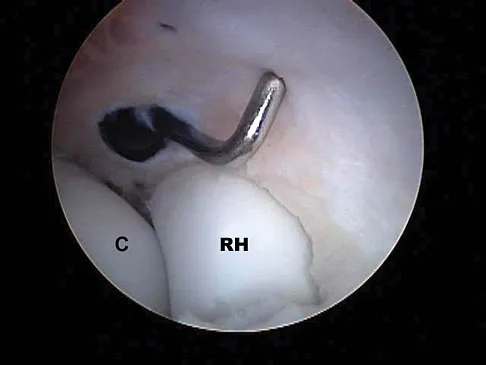

A 16-year-old boy with osteochondritis dissecans of the capitellum has intermittent symptoms of catching and locking. Examination is unremarkable. Radiographs reveal a loose body anteriorly with a diameter of 10 mm. To remove the loose body, elbow arthroscopy is being considered. Which of the following procedures would minimize the risk of neurovascular complication during the procedure?

Explanation